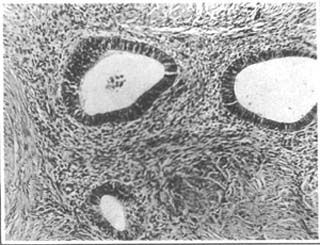

當子宮內膜和間質(zhì)侵入到子宮肌層時(shí)稱(chēng)為子宮肌腺癥。痛經(jīng)是子宮肌腺癥的最主要的癥狀。因為月經(jīng)期,異位灶內的子宮內膜與子宮內的內膜組織同樣發(fā)生出血和有大量前列腺素F2α的釋放,刺激全身平滑肌痙攣,引起子宮輸卵管痙攣和活動(dòng)異常,同時(shí)使子宮致密肌層出血,就引起劇烈的,甚至比子宮內膜異位癥更劇烈的痛經(jīng),而且逐月加重,很多患者即使服用止痛藥都無(wú)法緩解,甚至更嚴重的影響到日常生活和工作。通常這種時(shí)候,在藥物都無(wú)法緩解的情況下,西醫就只能是采取手術(shù)切除子宮了。